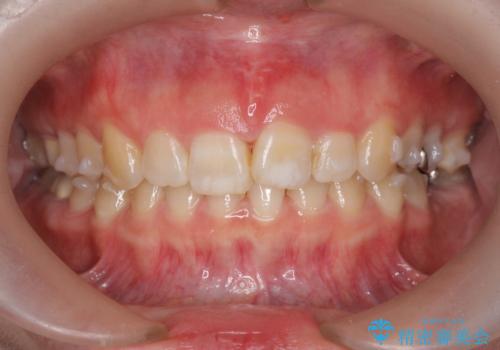

ねじれた前歯を改善するマウスピース矯正

- 大きくねじれた前歯をまっすぐに並べたい。と矯正治療を希望され来院されました。

前歯をきっちり並べるには奥歯の噛み合わせの調整を行い上下の前後的関係を治し、ねじれを取るスペースを確保していきます。

当初前歯だけ治れば良い、という心算で来院されましたが奥歯の噛み合わせも負担が大きく問題の起きやすいことをお伝えし上顎の奥歯をきっちりと後方移動行い噛み合わせの調整を行いました。・